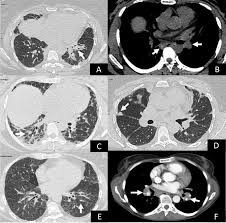

World map of Antisynthetase syndrome. ICD-10-CM Diagnosis Code G463 convert to ICD-9-CM Brain stem stroke syndrome. Antisynthetase syndrome Clinical manifestations Prevalence Myositis 90 Interstitial lung disease 60 Arthritis 50 Raynauds phenomenon 40 Fevr20 Mechanics hands 30 Lung involvement.

Antisynthetase syndrome Disease definition A rare idiopathic inflammatory myopathy IIM characterized principally by myositis generally symmetrical arthritis and interstitial lung disease ILD in association with serum autoantibodies to aminoacyl-transfer RNA synthetases anti-ARS. ICD-10-CM Diagnosis Code S14122D convert to ICD-9-CM Central cord syndrome at C2 level of cervical spinal cord subsequent encounter. Rüegg CA et al.

Antisynthetase syndrome is a set of symptoms that typically occur for patients who have myositis together with one of several specific autoantibodies known as antisynthetase antibodies. 816 Reticuloendothelial and immunity disorders without ccmcc.